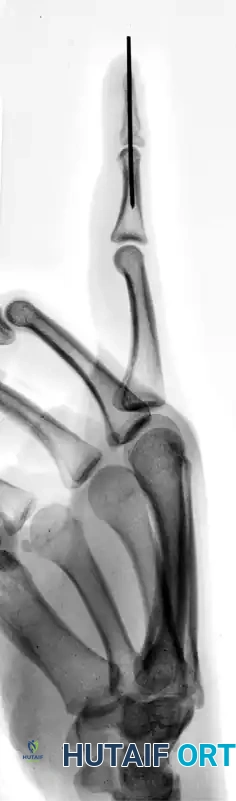

FIGURE 67-64 A and B: Displaced and angulated distal phalangeal fracture associated with a severe nail bed laceration in a 22-year-old patient, demonstrating the classic presentation of a complex open distal phalanx injury.

FIGURE 67-64 C and D: Postoperative radiographic and clinical appearance after precise bone fixation with a K-wire, which provided the necessary stability to permit subsequent realignment and microsurgical repair of the nail bed.